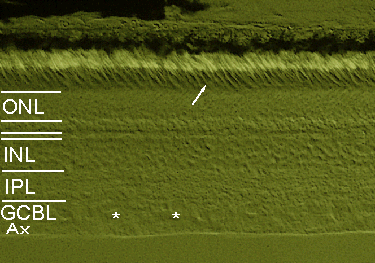

Section of the monkey retina approximately 10 mm away from the fovea (midperiphery of the eye) some of the retinal ganglion cells are marked by an asterisk. the arrow points at a cone, whereas most of the other photoreceptors are rods easily recognized by the light appearance of their outer segments. Note that the first layer indicated below the ONL is the row of photoreceptor axon terminals, i.e. cone pedicles and rod spherules (to name them correctly). Ax: Axons of retinal ganglion cells.